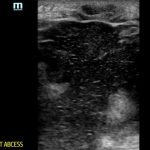

A 57-year-old male with a history of intravenous drug use presented to the emergency department with four days of progressively worsening pain and swelling to his left buttock after injecting heroin subcutaneously (i.e., “skin popping”). Labs were significant for a white blood cell count (WBC) of 26.7×103/mm3. Using the high frequency, linear probe, a point-of-care ultrasound (POCUS) was performed and revealed a large soft tissue abscess.

Point-of-care ultrasound reveals a large, hypoechoic soft tissue abscess with debris and tracks extending to the bottom of the image. Furthermore, when compressed, movement of the abscess contents is appreciated. There is also superficial cobble-stoning consistent with overlying cellulitis and soft tissue edema.

In the United States, there are over 14 million outpatient visits per year related to soft tissue infections, with nearly one-third being seen in the emergency department.1,2 22%-65% of intravenous drug users experience abscesses and cellulitis.3 Soft tissue abscesses are commonly encountered in the emergency department and the diagnosis is often made by history and physical exam.5 However, imaging modalities are more accurate than physical exam alone. When comparing ultrasound to physical exam in the diagnosis of soft tissue abscesses, one study suggests that ultrasound has a sensitivity and specificity of 96% and 87%, respectively. The sensitivity and specificity of the physical exam is 84% and 60%, respectively.4 Another study comparing computed tomography (CT) to ultrasound in the diagnosis of abscesses found ultrasound to have a sensitivity and specificity of 96.7% and 85.7%, respectively, while the overall sensitivity and specificity of CT was 76.7% and 91.4%, respectively. Ultrasound was superior in overall image detail ratings and demonstrated more visible detail within the abscess cavity. 5 When utilizing POCUS to evaluate for an abscess, look for an area of anechoic or hypoechoic fluid that may have contain septae, sediment, or gas. If one compresses the area with the transducer, movement or swirling of the abscess contents may be induced.